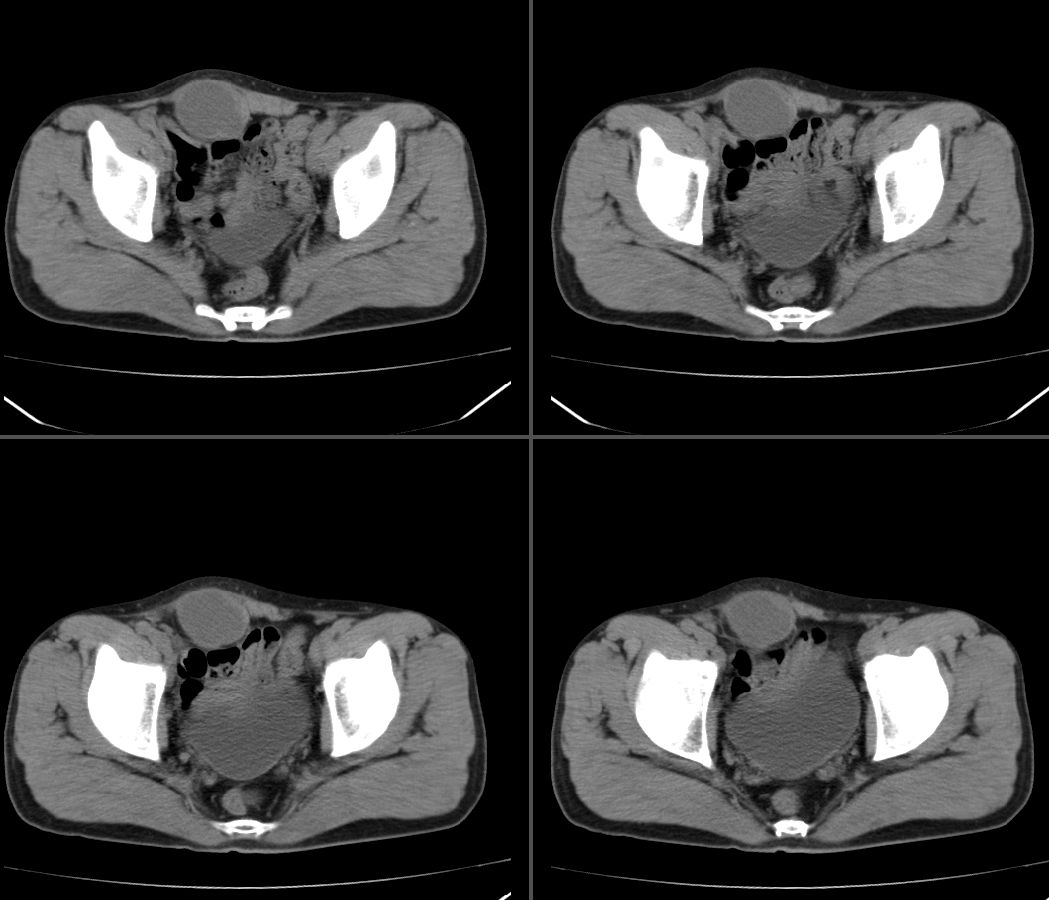

定位:右腹直肌鞘下部

病灶特点:分界清,边缘光整,囊性密度,病灶成长椭圆形,病灶处腹直肌受压萎缩,病灶与膀胱处有相似密度管状灶(该征象因肠道未作准备,不能确切)

右腹直肌腱鞘来源,韧带样纤维瘤可能性大,病变有侵袭性,右侧耻骨联合有骨质缺损。

前腹壁肿块,囊性变,右侧耻骨联合有骨质缺损。

右腹直肌腱鞘来源,耻骨联合有骨质缺损,考虑神经源性肿瘤